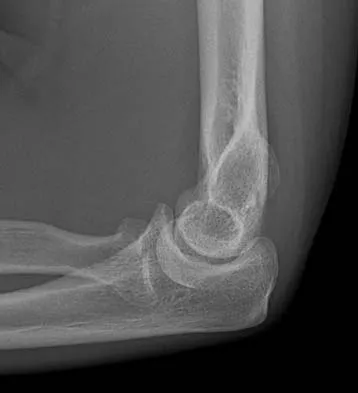

A 78-year-old woman falls onto her nondominant left elbow and sustains the injury shown in Figure 5. What treatment option allows her the shortest recovery time and highest likelihood of good function and range of motion?

Explanation

Total elbow arthroplasty has become the treatment of choice for complex, comminuted distal humeral fractures in patients older than age 70 years. It yields a faster recovery with more predictable functional outcomes, although limitations of lifting weight of more than 5 pounds must be followed to avoid loosening. Kamineni S, Morrey BF: Distal humeral fractures treated with noncustom total elbow replacement. J Bone Joint Surg Am 2004;86:940-947.